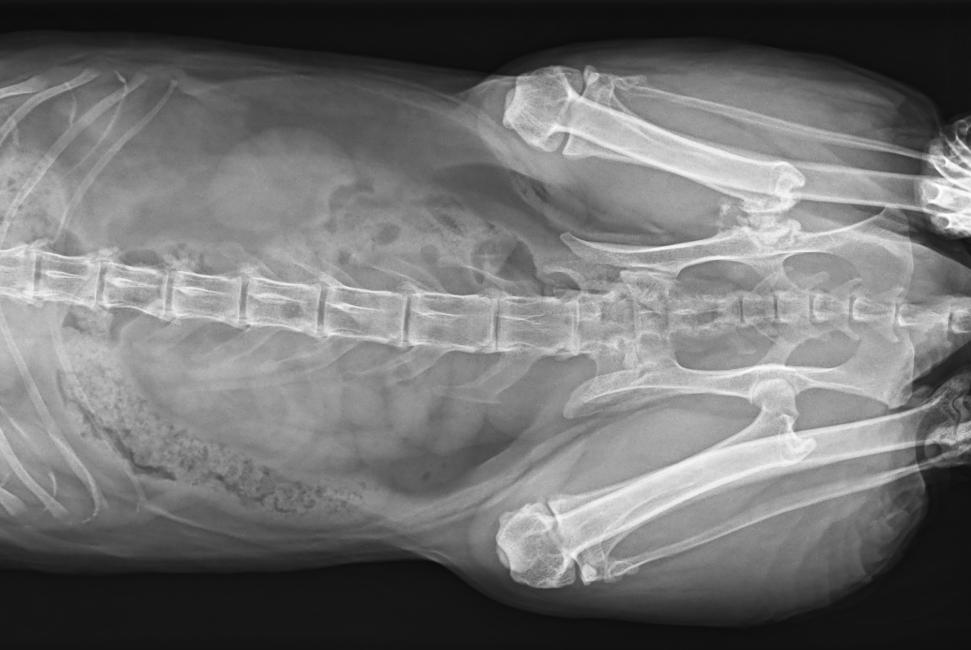

● 17*17大尺寸平板探測器,獲得高質量圖像

● 優(yōu)異的空間分辨率及信噪比,提升圖像質量

● 采用線噪聲消除技術,使成像質量提升40%

● 智能高效的圖像處理軟件,大幅提升圖像質量